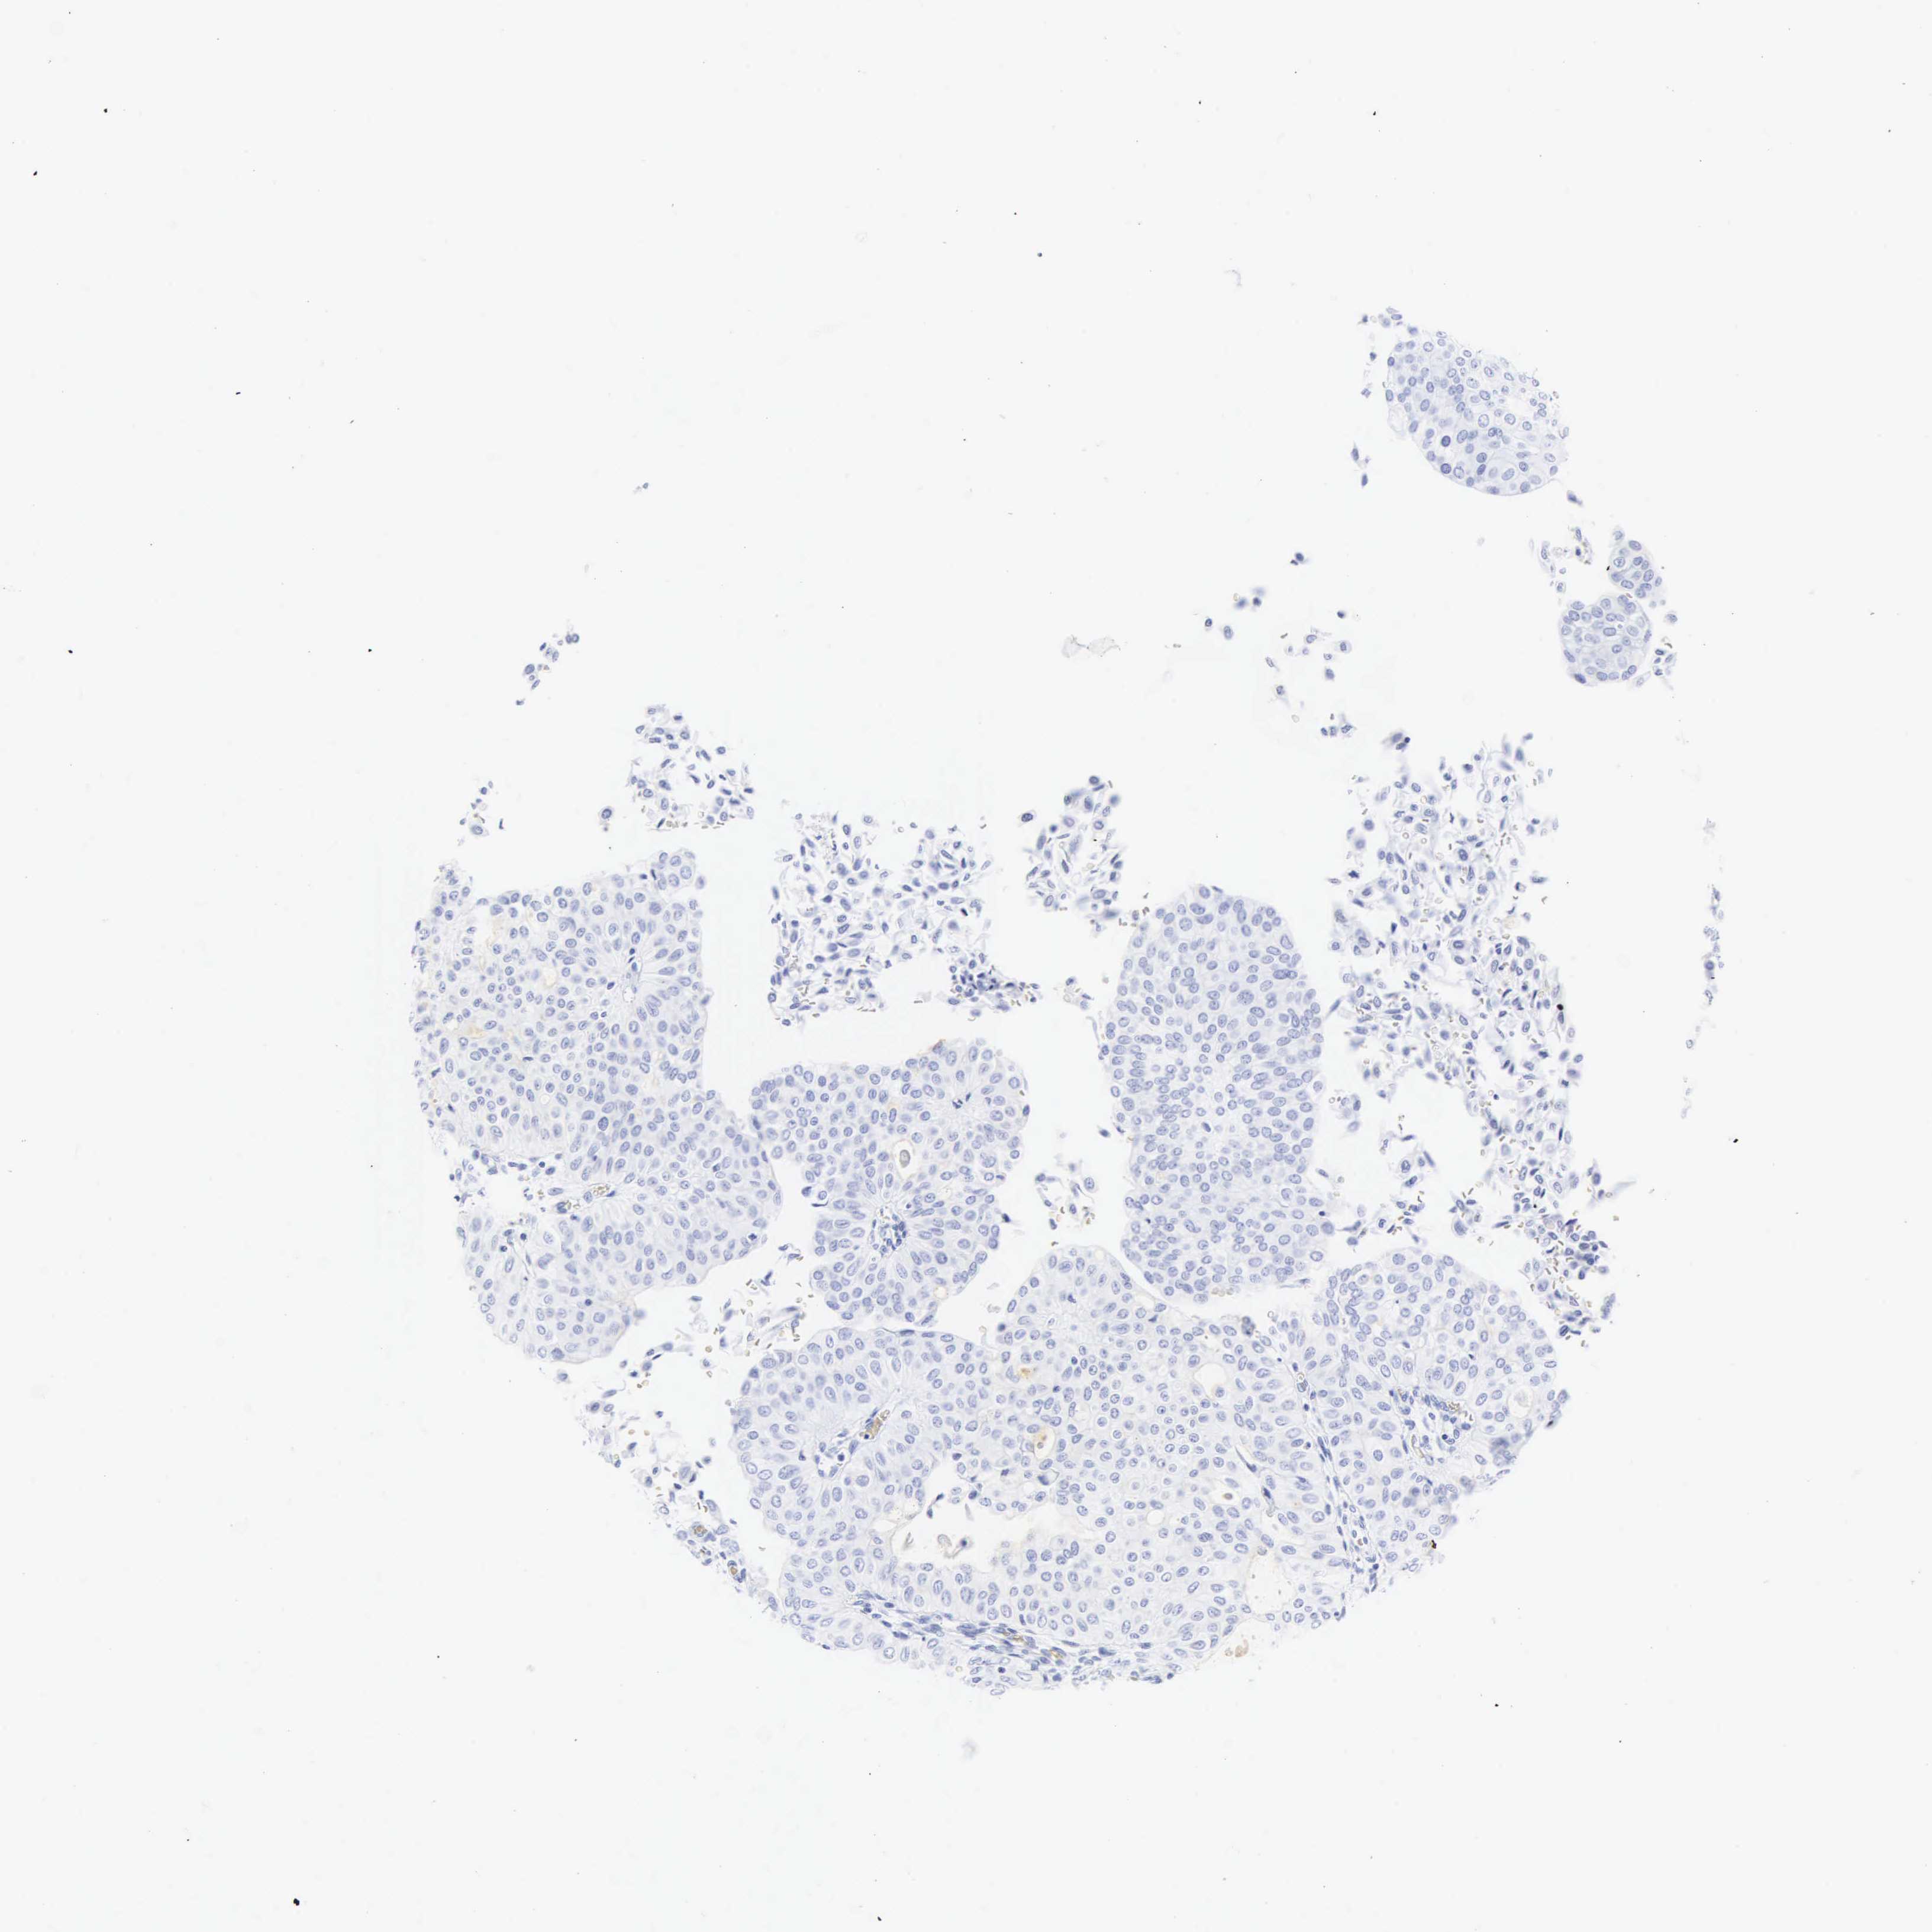

UROTHELIAL CANCER - Protein expressioni

A mouse-over function shows sample information and annotation data. Click on an image to view it in a full screen mode. Samples can be filtered based on level of antibody staining by selecting one or several of the following categories: high, medium, low and not detected. The assay and annotation is described here.

Note that samples used for immunohistochemistry by the Human Protein Atlas do not correspond to samples in the TCGA dataset.

Antibody stainingi

Antibody staining in the annotated cell types in the current human tissue is reported as not detected, low, medium, or high, based on conventional immunohistochemistry profiling in selected tissues. This score is based on the combination of the staining intensity and fraction of stained cells.

Each image is clickable and will lead to virtual microscopy that enables deeper exploration of all samples and also displays staining intensity scores, fraction scores and subcellular localization as well as patient and tissue information for each sample.

Antibody HPA038925

Antibody HPA038934

Antibody CAB000042

Antibody CAB010884

Staining

High

Medium

Low

Not detected

Intensity

Strong

Moderate

Weak

Negative

Quantity

>75%

75%-25%

<25%

None

Location

Nuclear

Cytoplasmic/membranous

Cytoplasmic/membranous,nuclear

Urothelial carcinoma, High grade

Urothelial carcinoma, Low grade

Adenocarcinoma, NOS